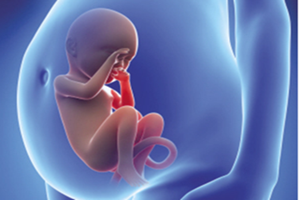

4、女人在进行四维彩超时,在进行检查的时候医生是需要进行仔细的检查的,一旦发现宝宝有异常变化的时候花费的时间会长点,在检查的时候主要是要检查宝宝的头部、如唇裂,大脑、骨骼发育不良,肾、心脏、脊柱裂,等,以便尽早的进行治疗,做四维彩超大概需要30分钟左右的时间。